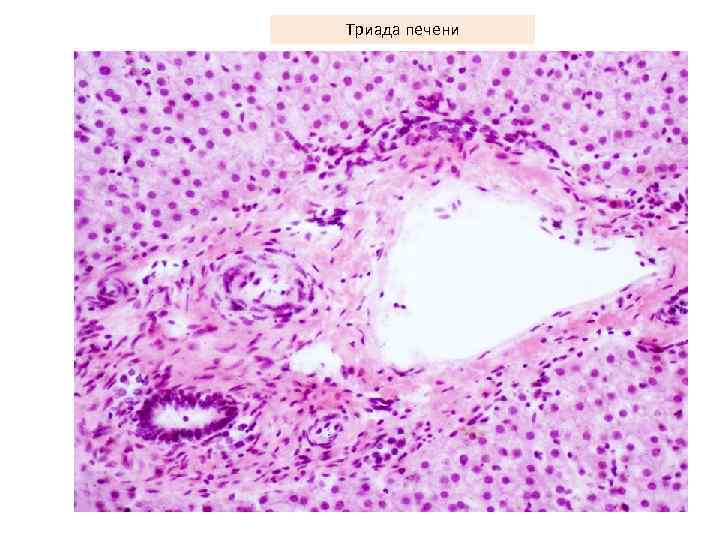

Триада печени

Триада печени